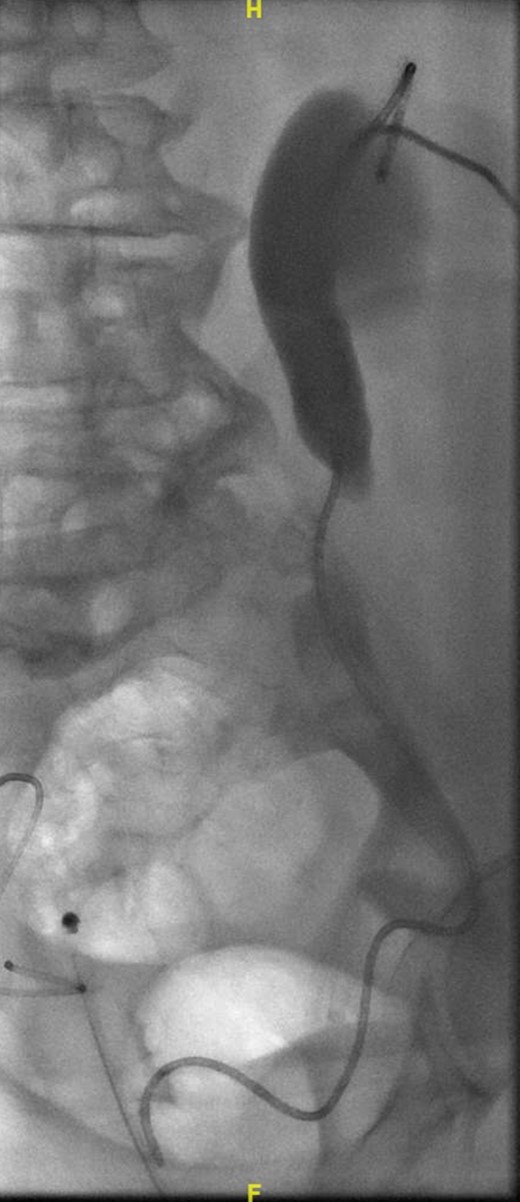

A week later, a left nephrostogram showed a capacious upper urinary tract with a deviated lower ureter which tapered in the pelvis with no filling defects seen above this level (Fig. 5). The appearances were in keeping with extrinsic compression. A week later, rigid cystoscopy, right-sided retrograde study, right JJ stent insertion and cystogram were performed. The left ureteric orifice could not be identified. The cystogram demonstrated no evidence of bladder herniation to the inguinal hernia (Fig. 6). Two months later, a non-contrast CT of the urinary tract demonstrated partial resolution of bilateral hydronephrosis, right-sided stent and left nephrostomy situated appropriately, persistence of left inguinoscrotal hernia and no other cause for ureteric compression. His eGFR was 34 mL/min when it was last checked a month prior to the non-contrast CT.

Six months following his admission, the patient was electively re-admitted for left-sided antegrade stent (Fig. 7) and removal of left nephrostomy. His renal function improved with an eGFR of 37 mL/min. He is awaiting elective repair of the inguinal hernia after which he will have bilateral removal of ureteric stents.